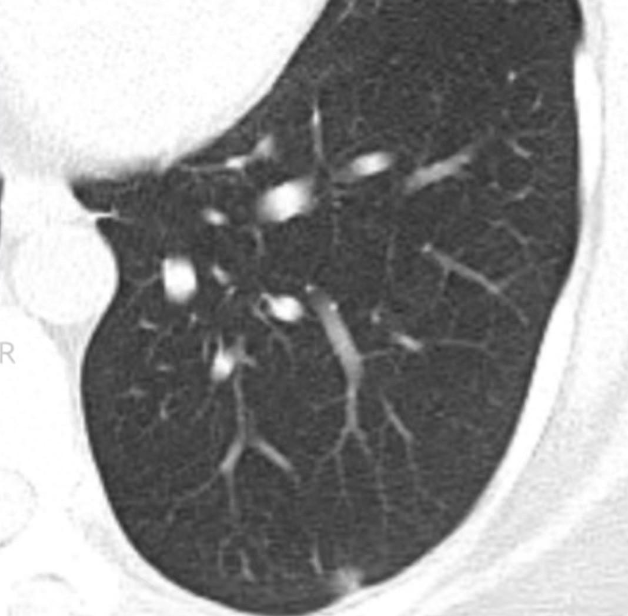

影像病理联合读片之肺原位腺癌

图片尺寸1080x810